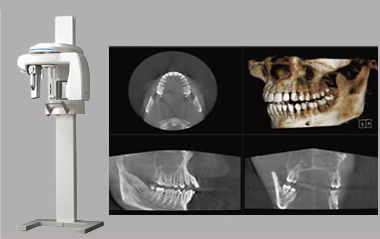

歯科用CT

より高度な診断と安全な治療を行うため、当院では全国でも数%の歯科医院でしか導入されていない歯科用CTを導入しております。 通常のレントゲンでは確認できない、顎の骨や神経の走行などの状態を細部まで3次元の立体で確認することができます。また歯科用コンビームCTの被曝線量は医科用の1/8と低水準なため安心していただくことができます。